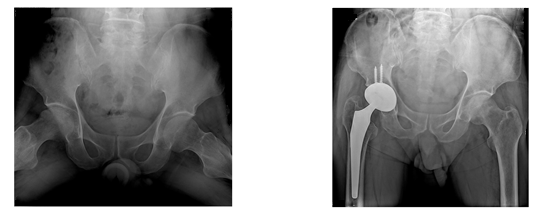

¾ûµ¢ÀÌ °üÀý(°í°üÀý)

°í°üÀýÀº üÁßÀÌ ¸ö¿¡¼ ÇÏü·Î Àü´ÞµÇ´Â ¸Å¿ì Áß¿äÇÑ °üÀý·Î ¿ì¸® ¸ö¿¡¼ µÎ ¹øÂ°·Î Å« °üÀýÀÔ´Ï´Ù. °üÀý¸éÀ» ÀÌ·ç´Â ´ëÅð°ñµÎ¸é°ú °ñ¹ÝÀÇ ºñ±¸¸é¿¡´Â ¿¬°ñÀÌ µ¤¿©ÀÖ¾î Ãæ°Ý Èí¼ö¿Í ÇÔ²² °üÀýÀÌ ºÎµå·´°Ô ¿òÁ÷ÀÏ ¼ö ÀÖ°Ô ÇÕ´Ï´Ù. ¶ÇÇÑ °üÀýÀ» ½Î°í ÀÖ´Â °üÀý¸·À̳ª ÀÎ´ë ±ÙÀ°µéÀÌ °í°üÀýÀ» ¾ÈÁ¤µÇ°Ô ÁöÁöÇϰí ÀÖ½À´Ï´Ù. µû¶ó¼ Á¤»óÀûÀÎ °üÀýÀº °È°Å³ª ±¸ºÎ¸®°Å³ª µ¹¸®°Å³ª ¸¹Àº üÁßÀÌ ºÎ°úµÇ¾îµµ ÅëÁõ ¾øÀÌ ¿øÈ°ÇÑ ¿îµ¿À» ÇÒ ¼ö°¡ ÀÖ½À´Ï´Ù.